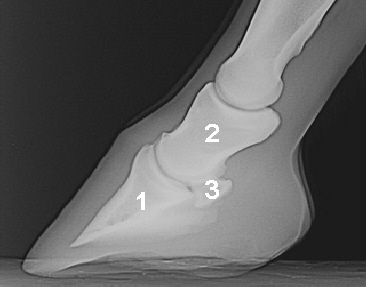

90° Aufnahme (Lateromedial, seitliche Aufnahme)

Diese Aufnahme für die Beurteilung des Strahlbeins gut zu schießen, ist gar nicht so einfach. Das Pferd sollte auf einem Brett stehen und die Gliedmaße plan belasten. Der Zentralstrahl muss von der Seite mit 90° genau auf das Strahlbein treffen, um eine schiefe Darstellung zu vermeiden (1,5-2cm unterhalb des Kronsaumes auf die verlängerte Verlaufslinie der Beugesehne). Übersichtsaufnahmen der Zehenachse, bei denen der Zentralstrahl höher liegt sind für eine exakte Strahlbeinbeurteilung meist nicht ausreichend. Der Zentralstrahl muss parallel zu den Ballen gerichtet sein, um ein verzerrungsfreies Bild zu erhalten  (zur Hilfe Stab auf den Boden legen).

1 Hufbein, 2 Kronbein, 3 Strahlbein